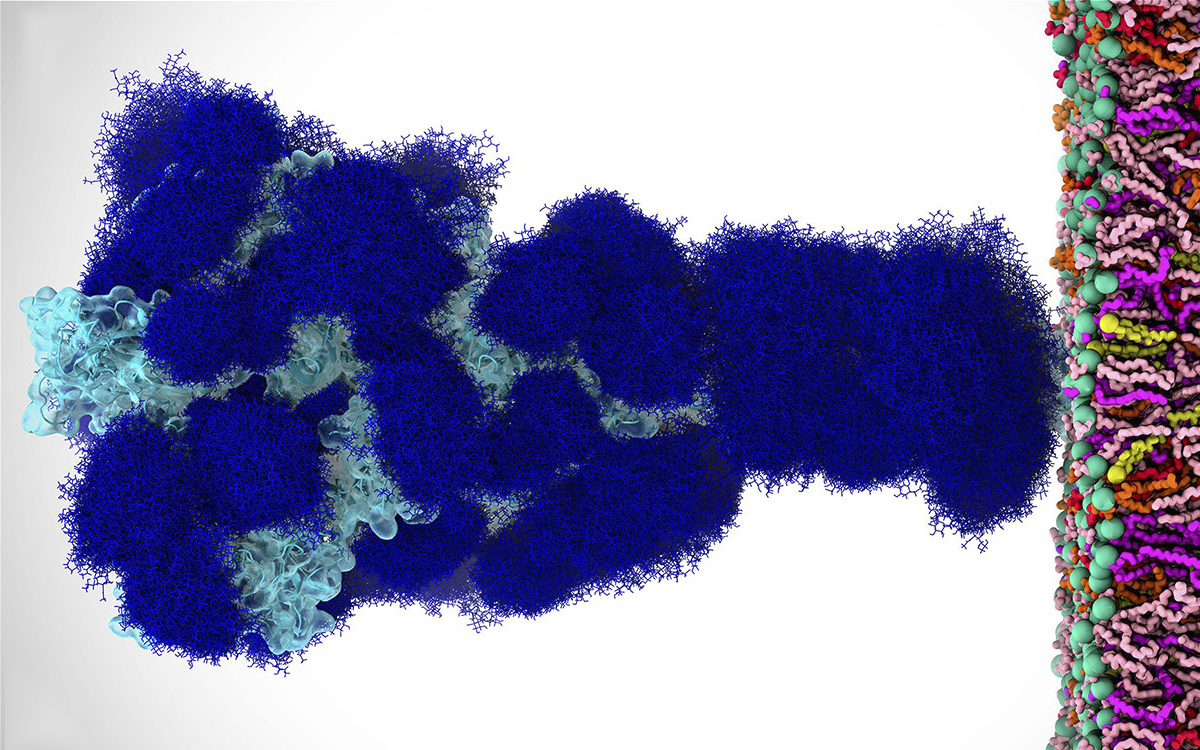

Descubren que las ´espinas´ del coronavirus están cubiertas de azúcar

Un grupo de científicos de la Universidad de California San Diego publicó en septiembre del año pasado, un trabajo de investigación que demostró que el azúcar -concretamente los glicanos- juega un papel fundamental para que el virus SARS-CoV...